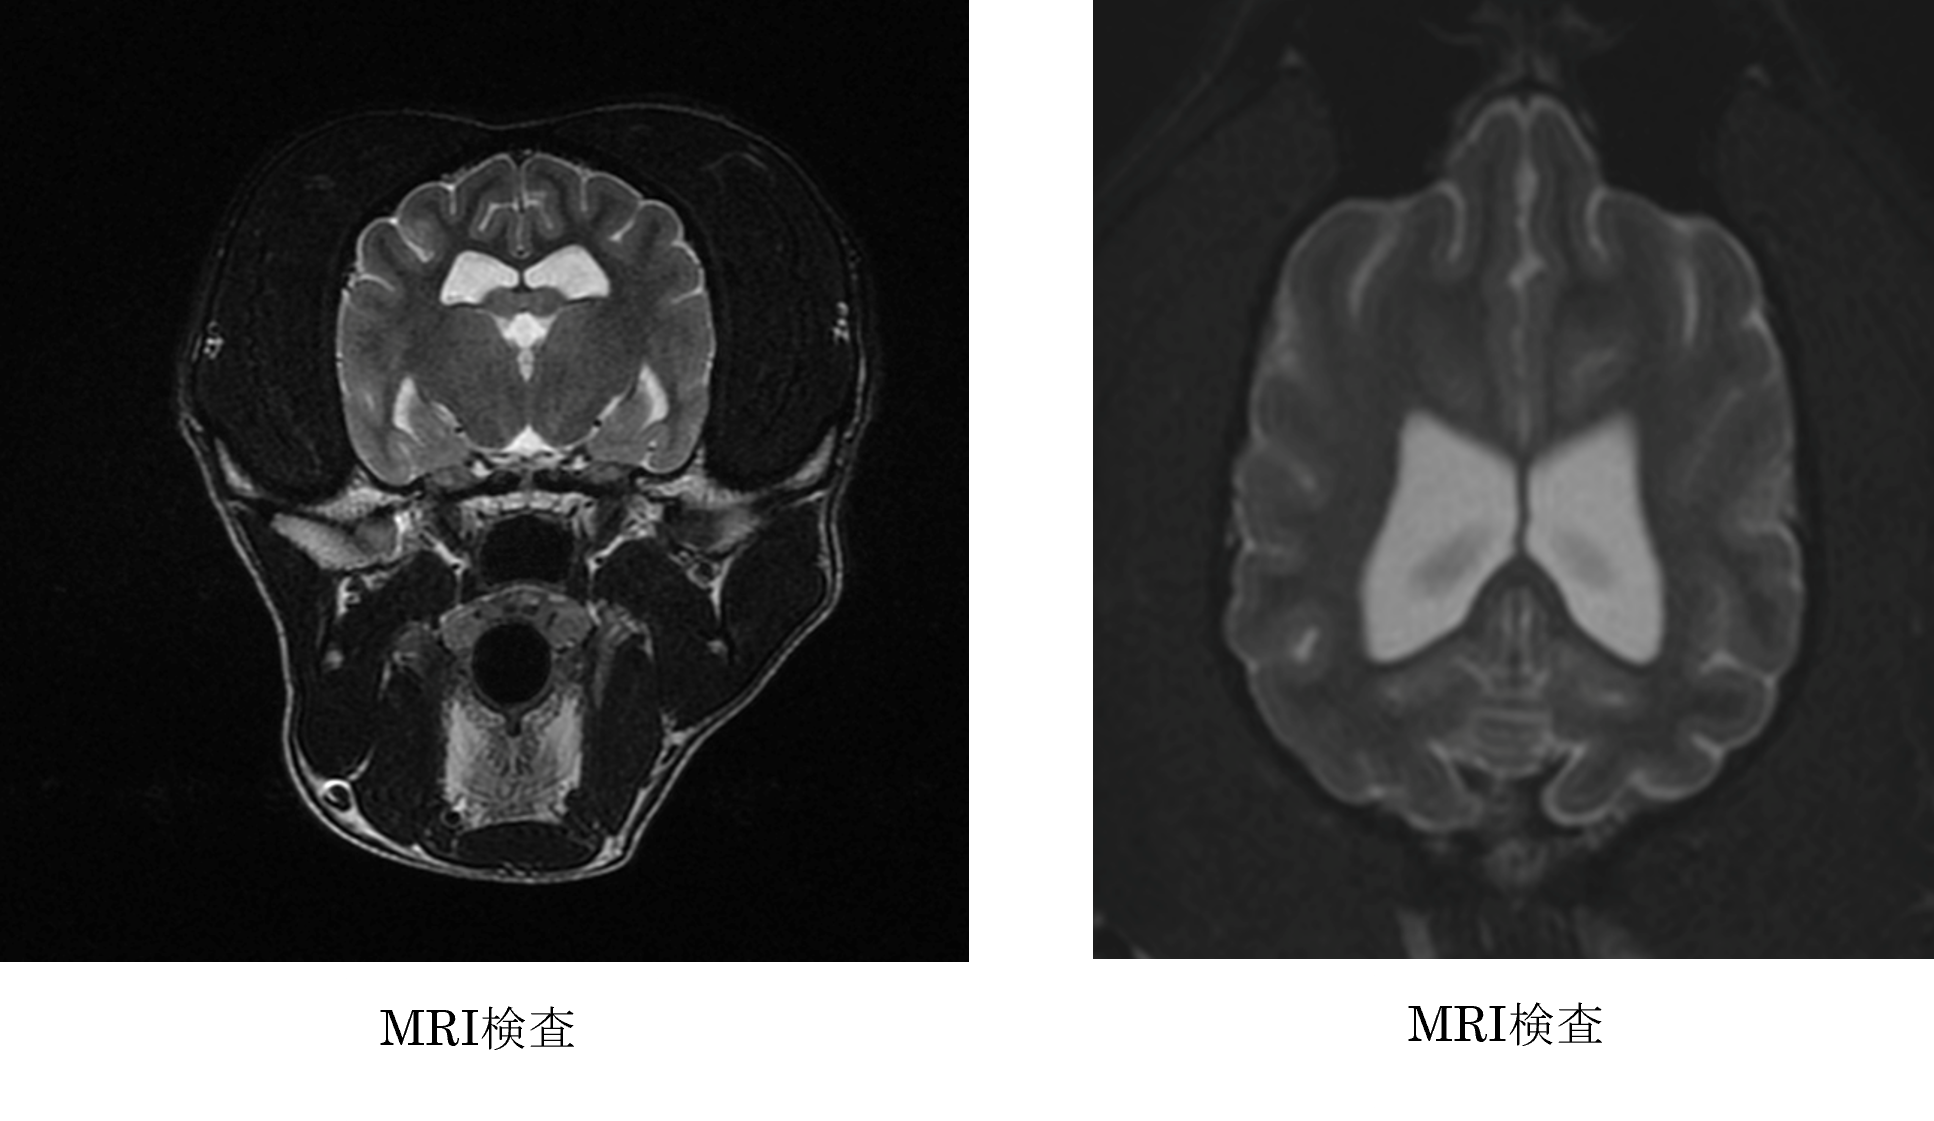

各種検査より、頭蓋内による発作の可能性が高いためMRI検査が重要と判断しました。

ご家族と相談した結果、MRIおよび脳脊髄液の検査を行いました。

MRIおよび脳脊髄液検査より特発性てんかんと診断し、抗てんかん薬を行いました。